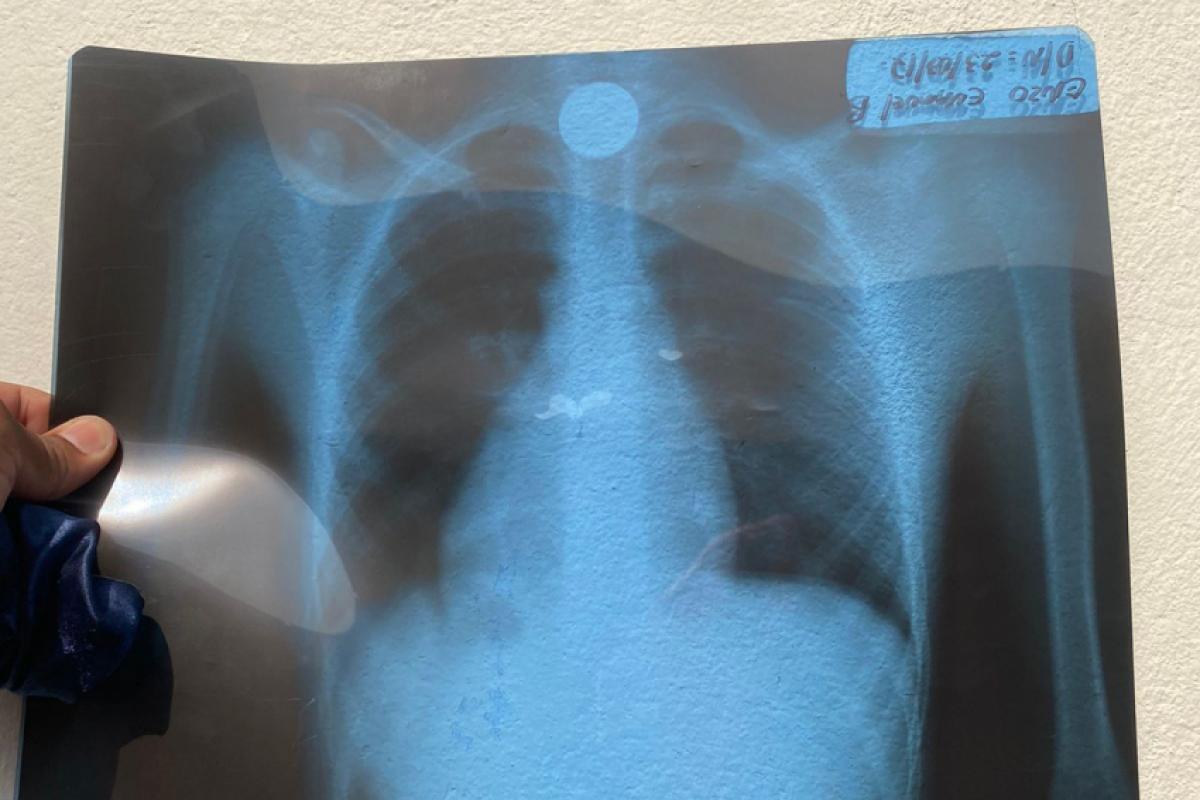

Raio-X: Moeda ficou presa na garganta da criança de 7 anos

Na UPA, a criança fez um exame de raio-X para verificar a posição da moeda na garganta. Com o resultado em mãos, constataram que se tratava de uma situação de risco, e ele foi transferido para o Pronto-socorro Infantil 'Doutor Magid Bachur Filho', localizado na região central. Na unidade de saúde, a criança ficou aguardando vaga para a Santa Casa.